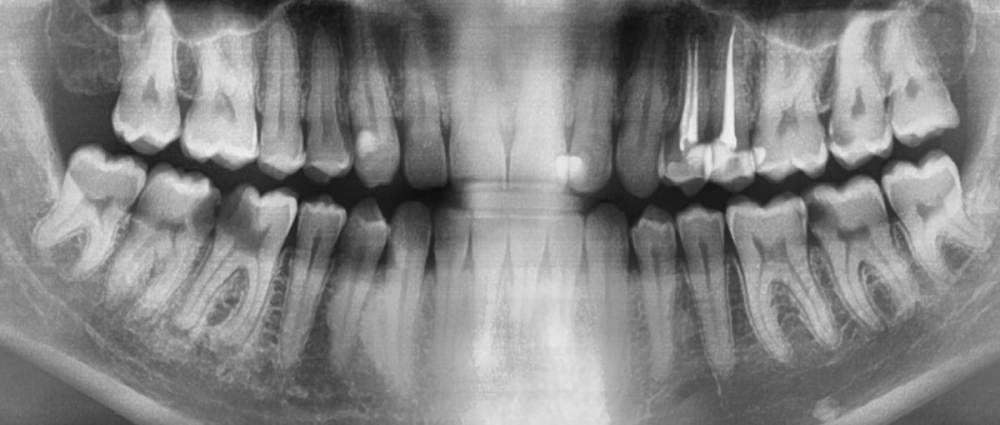

Elcirami Опубликовано 26 марта, 2021 Поделиться Опубликовано 26 марта, 2021 Собственно вопрос в шапке. Правая нижняя 6 и 7. Если с 6 все понятно, и ей займусь после левых зубов, то вот касательно 7 есть вопрос. Стенка есть хоть и не значительная, но отсутствует реакция на холод тепло. Эод не проводился. Но, если судить по тому, как себя вел соседний зуб (а он как вы понимаете уже отправился в вальгаллу, осталось почистить, да под коронку) и зеркально зуб с левой стороны (уже под временной пломбой) отсутствие боли еще не показатель смерти нервно-сосудистого пучка. Врач, у которого я лечусь, говорит, что шансов спасти пульпу от удаления практически нет, стенка слишком тонкая, даже если все живо - слишком высок шанс вскрыть. Собственно это и есть вопрос, если жива, то стоит ли рисковать? Есть способы очистки не экскаватором и бором, а, например, химическим травлением каким - нибудь и стоит Скрытый текст поискать другого врача персонально для этого зуба? Или не жалеть, да отпустить и забыть? И еще вопрос, почему у меня весь кариес начинается между, хотя пользуюсь нитью и ополаскивателями (зубного камня мало и раз в 1-2 года счищаю). Спасибо за внимание. Ссылка на комментарий

red_butler Опубликовано 30 марта, 2021 Поделиться Опубликовано 30 марта, 2021 26.03.2021 в 18:15, Elcirami сказал: Врач, у которого я лечусь, говорит, что шансов спасти пульпу от удаления практически нет, судя по снимку, это так 26.03.2021 в 18:15, Elcirami сказал: И еще вопрос, почему у меня весь кариес начинается между, хотя пользуюсь нитью и ополаскивателями (зубного камня мало и раз в 1-2 года счищаю) покажите фото во рту, скорее всего уровень индивидуальной гигиены не достаточный Ссылка на комментарий